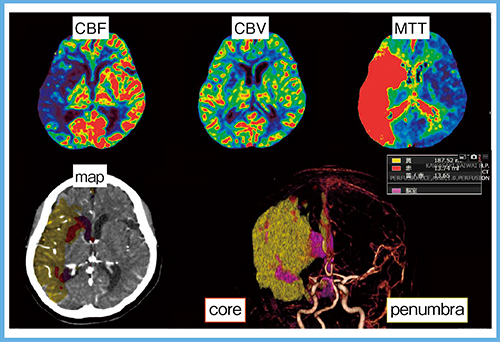

Vitreaでは,coreとpenumbraを分布マップと体積(数値)で表すサマリーマップも表示できる(図2)。サマリーではcore体積が50mLを超えていることから,発症2時間の症例であるが,推奨グレードC1に分類され,血栓回収療法の適応は慎重に検討すべき症例となる。数値化により,治療適応の正確な判断につながると考える。

図2 症例1:サマリーマップ

症例2は,NIHSS 20点の重症な脳梗塞で,右中大脳動脈閉塞,CT ASPECTSは放線冠を除くと7点であった。ベイジアンアルゴリズム解析では,penumbra体積が187mL,core体積が13mLであった(図3)。発症7時間ではあるが,core体積が25mL以下であることから推奨グレードはAとなり,血栓回収療法の良い適応となった。